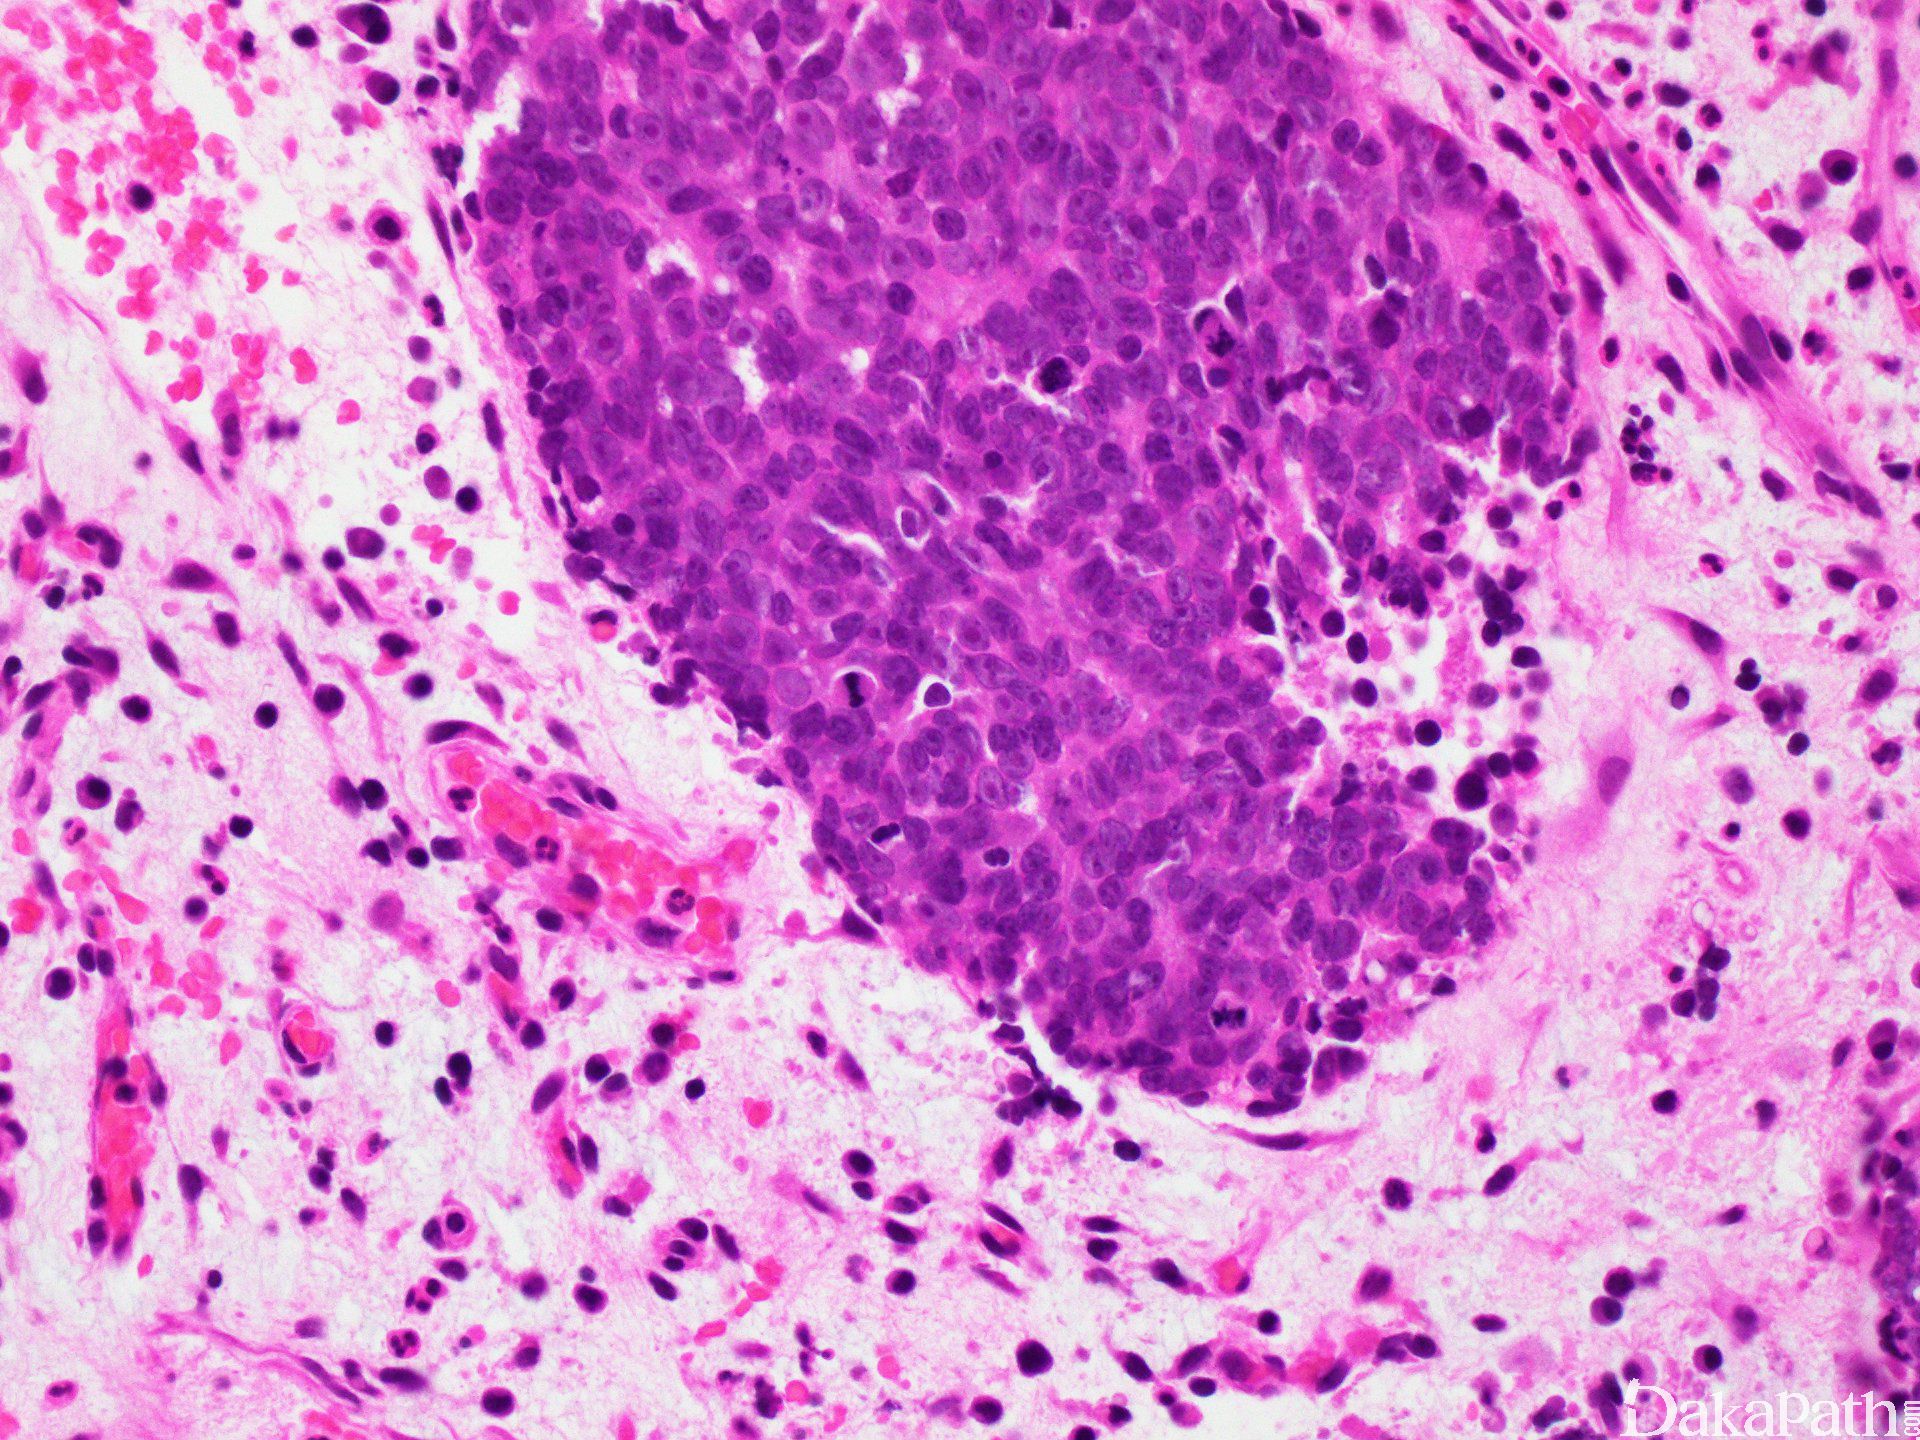

镜下肿瘤细胞丰富,呈叶状(器官样)、梁状、实性、片状或带状分布,细胞呈中至大多边形、圆形至卵圆形,核染色深或泡状核,模糊至显著核仁,胞浆多少不等,嗜酸,胞界不清,但部分细胞呈清晰边界,胞浆透明。核浆比高,核分裂像增多,可见非典型核分裂,显著肿瘤坏死及凋亡。

可见淋巴血管浸润及神经侵犯。